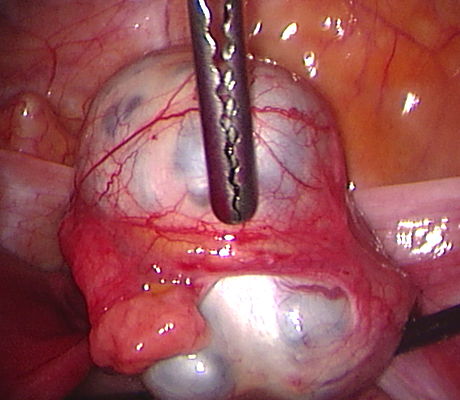

Examples of some pelvic masses dealt with by key-hole surgery.

Pelvic Mass